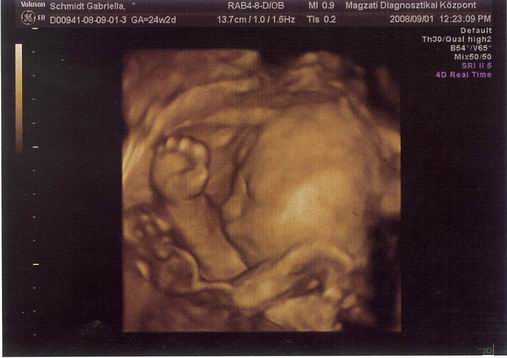

Mi szombaton reggel 8-ra megyünk a 4D Genesisbe kukucskára! :D Meg külön kérem, hogy nézzenek rá a kis agyára is a 2,5 héttel előrébb járó feje miatt.

Lufifejű magzatom értékei:

24+1:

BPD: 66mm, ennek megfelelő terhességi kor: 26+6

FL: 42mm, terhességi kor: 23+3

AC: 192mm, terhességi kor: 23+4

Egy cseppet aránytalan szegénykém. :roll: :?

Azért az más, ha a buksi meg a poci is nagyobb és a combcsont van elmaradva. Ebben az esetben max. kicsit alacsonyabb lesz. Szerintem ez nem összehasonlítható az én babám aránytalanságával, aki mindenben jó, csak a bucija nagyobb 2,5(!) héttel. :) Azért köszi.